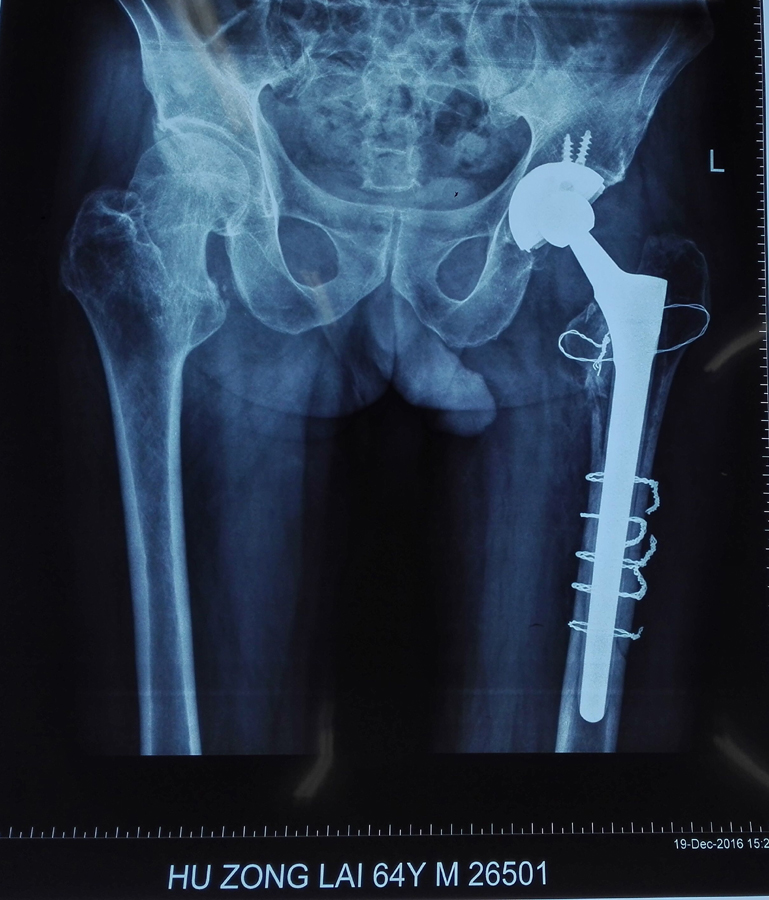

图2.翻修后

近日,我院成功为一名65岁的男性患者实施了假体周围骨折翻修手术。患者3年前在其他医院曾经做过全髋置换术,一周又前因为摔伤而导致假体周围骨折。据主刀医生胡勇主任介绍,该例假体周围骨折根据Vancouver分型为B2型,假体失去稳定性,需行髋关节假体翻修术。手术十分顺利,术后恢复满意,患者顺利出院。